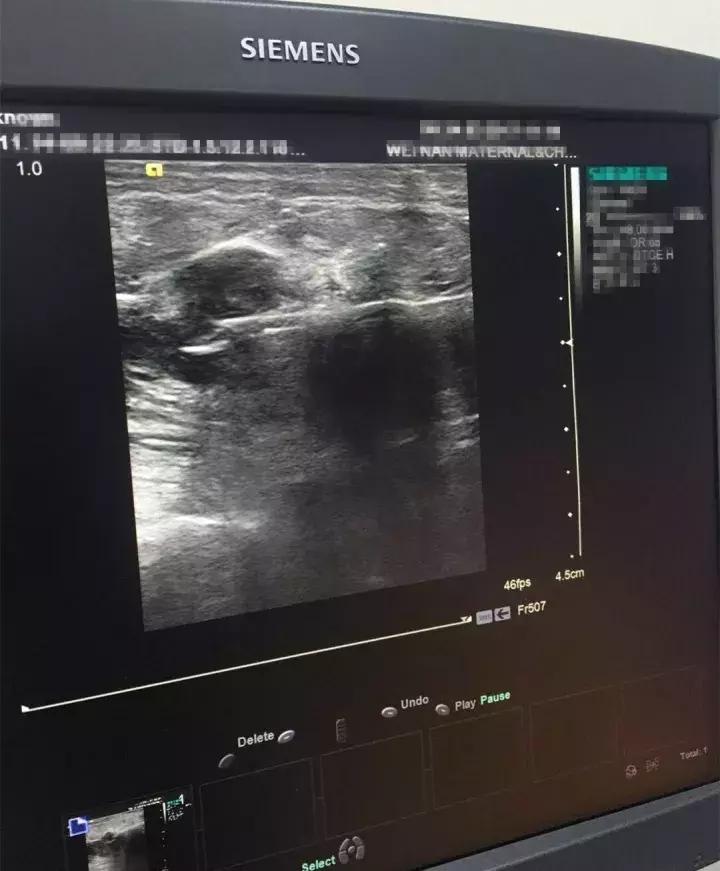

指在超声引导下用特制(专用)穿刺针刺入乳房肿块内取得活组织或者细胞学检查,确定乳房肿物性质的一种检查手段,需要在乳腺外科、超声科和病理科医生协作完成。超声科医生根据患者的病史及影像学资料,在穿刺时使用高频超声进行定位,外一科准确进行乳房肿物穿刺取材,及时送病理检查,根据病理报告确定下一步治疗。